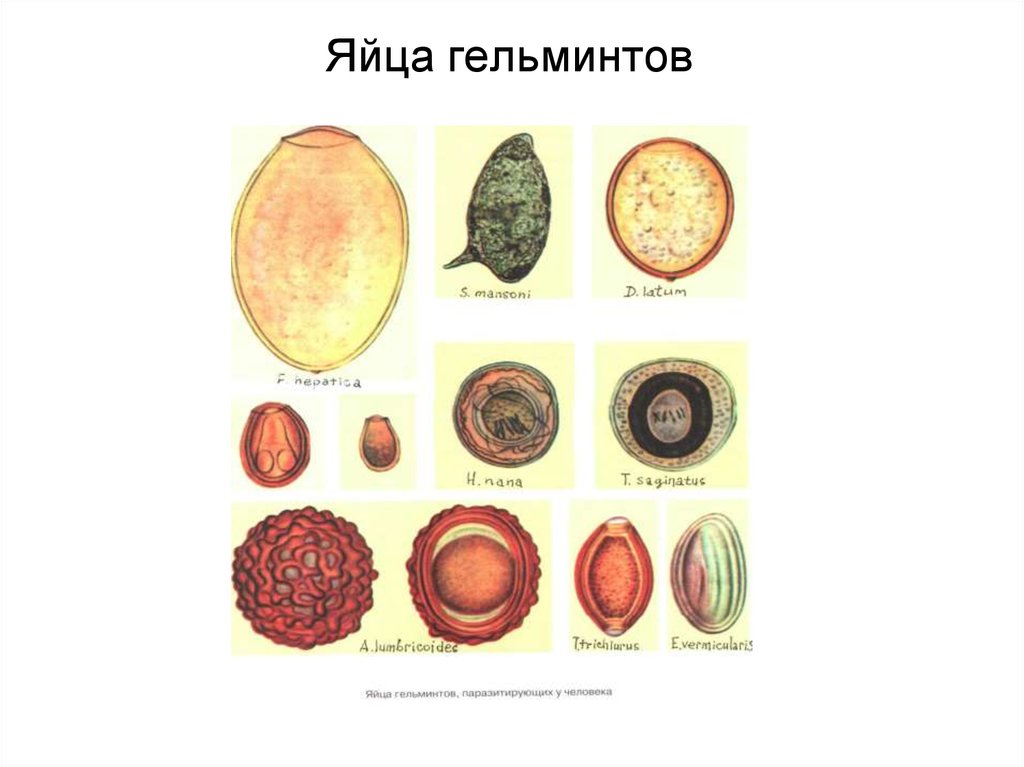

Микрофотографии яиц гельминтов Toxocara canis

Раздел: Фотоэссе